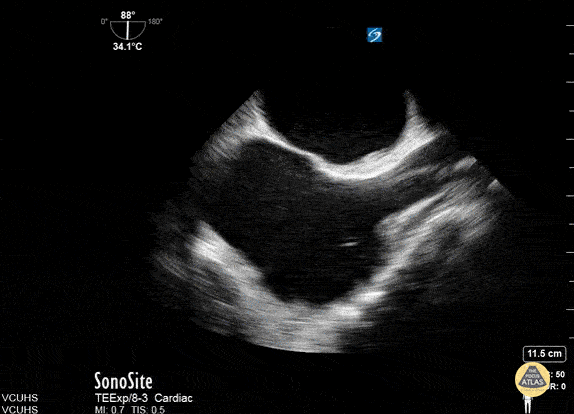

TEE confirmation of ECMO Cannula done at VCU. Dr. Stenberg